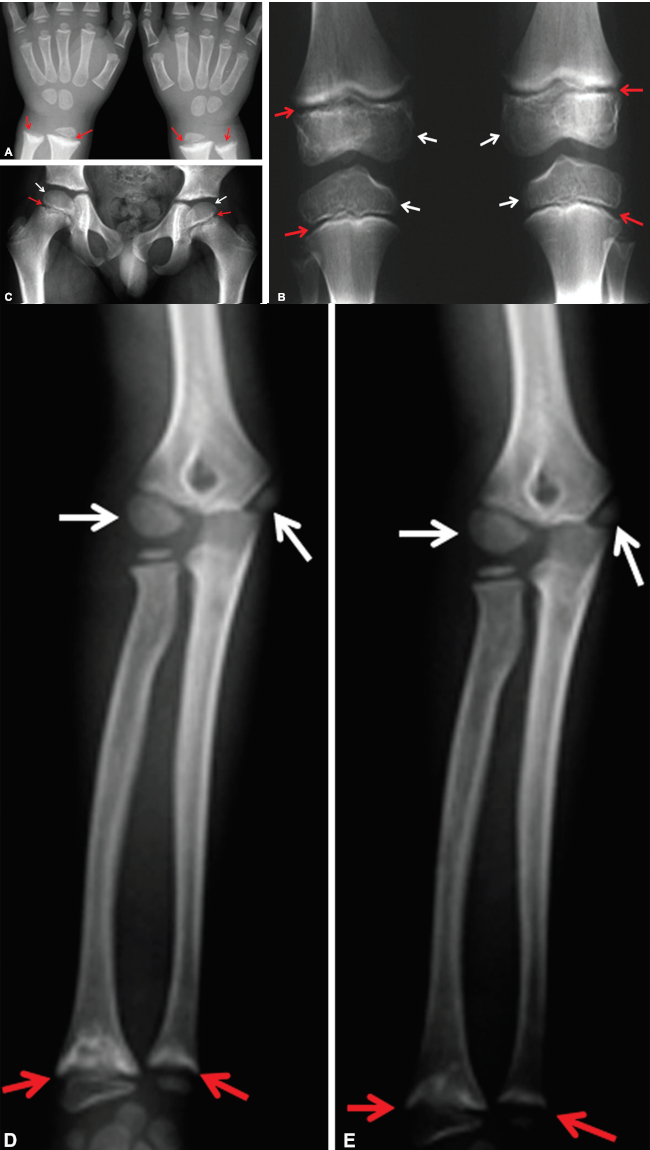

En los huesos largos, se observaban lesiones radiotransparentes que determinan irregularidad de las regiones metafisarias (3a y 3b) y deformidad de las epífisis de los fémures (3b y 3c), tibias (3b) y húmeros (3d y 3e) (►Fig. 3).

Los hallazgos radiológicos específicos observados en nuestro paciente, principalmente en las vértebras, la porción distal del radio y del cúbito y las rodillas, permitieron diagnosticar SPENCD.2,3 En una publicación, Schorr y col.4 plantearon el diagnóstico de SPENCD en base a los hallazgos óseos, que comprenden la presencia de platispondilia de grado variable, con irregularidad de los platillos vertebrales superior e inferior, presencia de lesiones nodulares localizadas inicialmente (o solo) en el tercio o la mitad posterior del cuerpo vertebral y lesiones no osificantes radiotransparentes, en sacabocados, redondeadas o multilobuladas que se extienden desde el cartílago de crecimiento a la metáfisis y diáfisis. Esas lesiones pueden ser de gravedad variable y aparecer solo en los huesos largos (típicamente en la zona distal de la rodilla, peroné proximal, radio distal y cúbito), pero también pueden observarse en otros sitios de crecimiento endocondral, como la cresta ilíaca.4,5